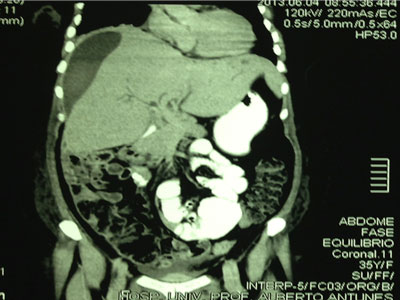

RM do Abdome Superior

Exames Complementares

Hipótese Diagnóstica

- Colangite;

- Estenose da anastomose.